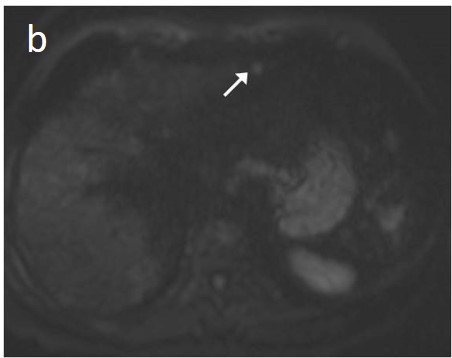

As already stated, small lesions (smaller than 1, 1.5, or 2 cm, depending on the publication) more often demonstrate atypical imaging features [135,136]. That is to say that lesions below the threshold of 1 cm cannot be characterized as HCC and follow-up is advised according to both EASL and AASLD guidelines. Small arterially-enhancing lesions may represent arterioportal shunts, perfusion disorders, or small intrahepatic cholangiocarcinomas (which may also show portal wash-out) [60]. Interval increase in size by ³50% in ≤6 months is a major feature according to LI-RADS (Figure 11). However, it is not accepted by EASL and any lesion growth or change in enhancement pattern not typical of HCC should call for biopsy [4].

Figure 11. This 48-year-old woman with a history of β-thalassemia major and cirrhosis was followed-up after successful locoregional treatment of two small HCCs. In liver segment II, a 5-mm high T2 signal focus is seen in an anterior subcapsular location (a) with associated restricted diffusion (arrow) (b). The lesion shows arterial enhancement (c) and no uptake of the hepatospecific contrast on the hepatobiliary phase (d). Although findings are highly suspicious, the lesion cannot be definitely characterized as HCC, due to its small size. On the subsequent follow up CT, interval growth and typical wash-in/wash-out are now present (e,f).